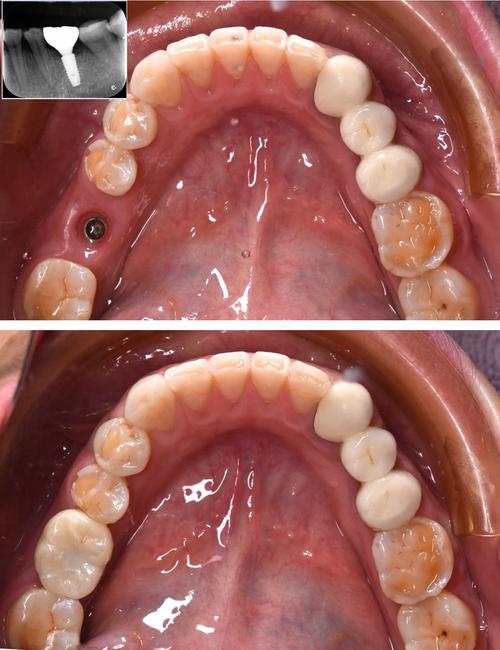

(图片来源网络,侵删)- 恢复期: 种植牙手术本身(尤其是单颗或多颗种植)通常需要一定的恢复时间(几天到几周不等),中秋节是法定假日,有连续几天休息,患者可以利用这段时间更好地休息、观察恢复情况,避免影响工作或学习。

- 复诊安排: 种植牙治疗通常需要多次复诊(如术前检查、手术、戴牙冠等),假期时间相对充裕,方便安排这些复诊,减少请假次数。

(图片来源网络,侵删)

(图片来源网络,侵删)- 种植牙是一个需要时间的生物过程(骨结合)。切勿为了在节日前完成而缩短必要的治疗周期(如骨结合时间不足就戴牙冠),否则可能导致种植失败,医生会根据你的口腔条件制定合理的治疗计划。